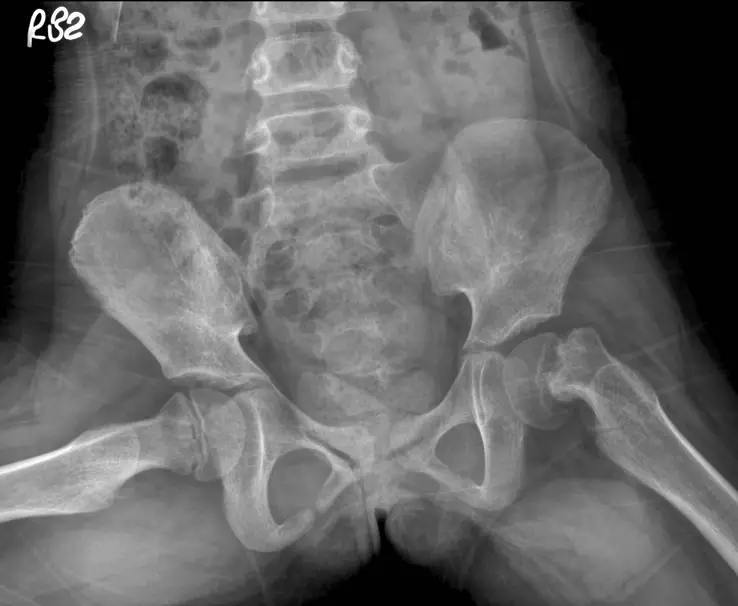

15 歲男生因鼠蹊部疼痛跛行而求診,其青蛙姿勢 X光如圖示,則最可能診斷為何?

本題考核青少年髖關節疾病的影像診斷,重點為股骨頭骨骺滑脫症(slipped capital femoral epiphysis, SCFE)在青蛙姿勢 X 光(frog-leg lateral view)上的典型表現。SCFE 是青少年最常見的髖關節疾病,好發於青春期肥胖男孩。

青蛙姿勢骨盆 X 光(frog-leg lateral pelvic radiograph):

影像標記顯示右側("R82",即患者右側,影像左方)髖關節有異常。比較雙側髖關節:

左側髖關節(影像右方): 外觀正常,股骨頭位於股骨頸正上方,股骨頭骨骺(femoral head epiphysis)與股骨頸的解剖關係正常,呈現正常的「冰淇淋球在甜筒上(ball on cone)」關係。

右側髖關節(影像左方): 股骨頭骨骺相對於股骨頸呈現向後下方(posteromedially)移位的現象。股骨頭骨骺看起來「向後滑落」,使股骨頸相對突出向前上方,呈現典型的「冰淇淋球從甜筒滑落(ice cream slipping off the cone)」外觀。

Klein 氏線(Klein's line)評估: 在正位(AP)觀,沿股骨頸上緣畫一條線(Klein 氏線),正常情況下此線應與股骨頭骨骺外側部分相交。SCFE 時,由